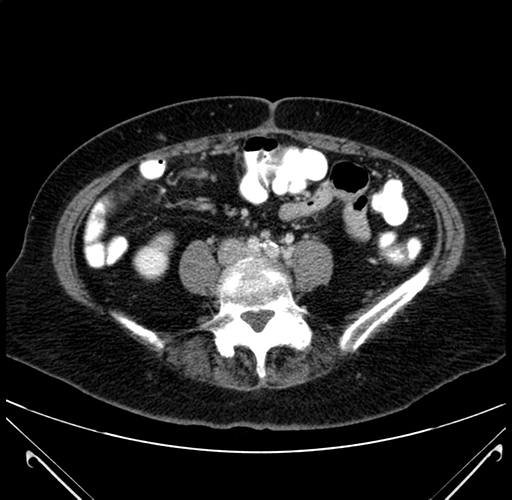

Coronal Venous